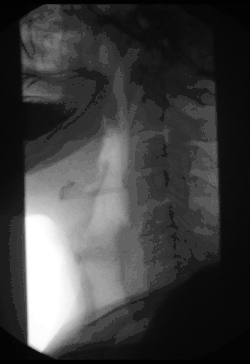

La fluoroscopie, ou radioscopie, est une modalité de la radiologie médicale qui consiste à acquérir en instantané des images dynamiques de l'intérieur des structures.

Un système de fluoroscopie est constitué d'un générateur de rayons X capable d'émettre des rayons X pendant plusieurs minutes de manière continue ou de manière pulsée. Initialement, l'image se formait sur un écran fluorescent. Sur les appareils modernes, l'image est acquise au moyen d'un amplificateur de brillance ou de certains capteurs plans capables de fonctionner en acquisition continue. Les images sont rapatriées en instantané vers un écran à partir duquel les opérateurs les analysent.

La technique est principalement utilisée en médecine pour le suivi en temps réel d'opérations chirurgicales[3], pour certains examens où l'évolution de produits injectés dans le corps du patient est suivie à l'écran, ou pour le positionnement précis de patients dans des appareils de radiothérapie ou de protonthérapie.